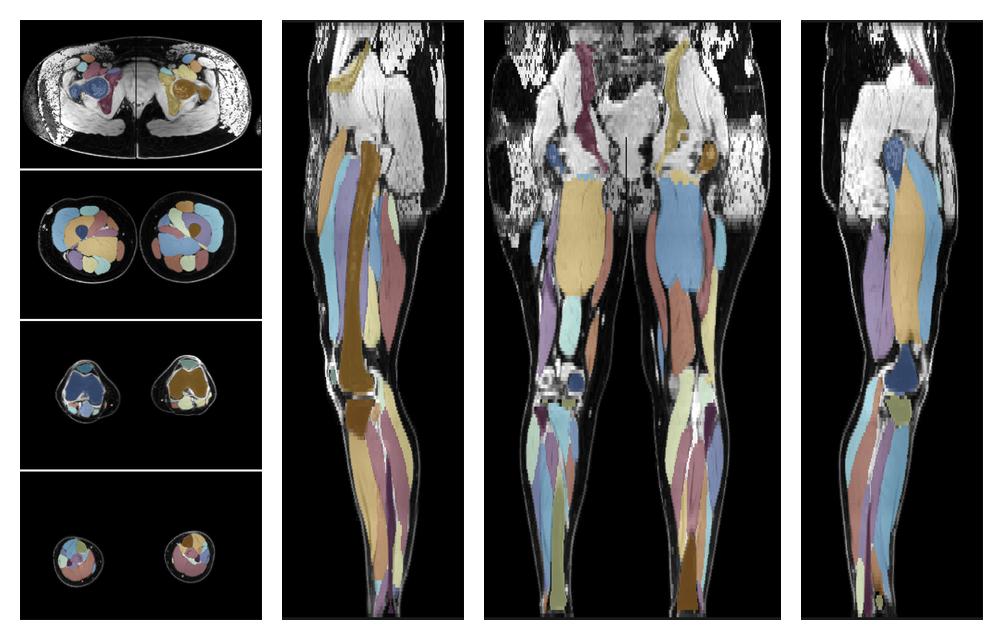

• Automated muscle and bone segmentation.

Overlay of automated muscle segmentation labels on dixon water image.